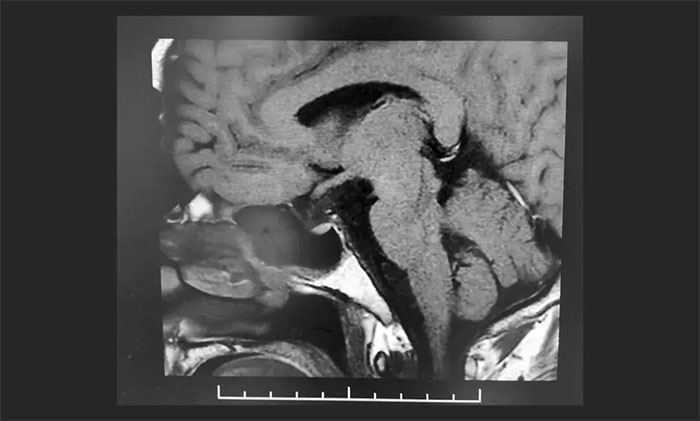

顱咽管瘤是位于鞍區(qū)或鞍旁區(qū)的生長(zhǎng)緩慢的中樞神經(jīng)系統(tǒng)良性腫瘤。起源于顱咽管的上皮細(xì)胞或 Rathke's囊的殘留(造釉型)或由原始口凹?xì)埩舻镊[狀上皮細(xì)胞化生而來(lái)(乳頭型)。顱咽管瘤可從垂體下丘腦軸的任何一點(diǎn)發(fā)生并沿此軸發(fā)展,腫瘤可從位于蝶鞍到大腦的第...[詳細(xì)]